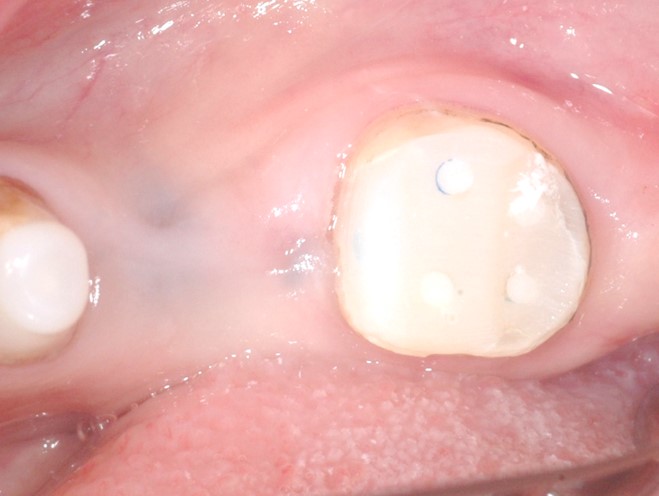

まず周りにホール(穴)を形成します。(下写真:赤点線部分に歯髄がある)